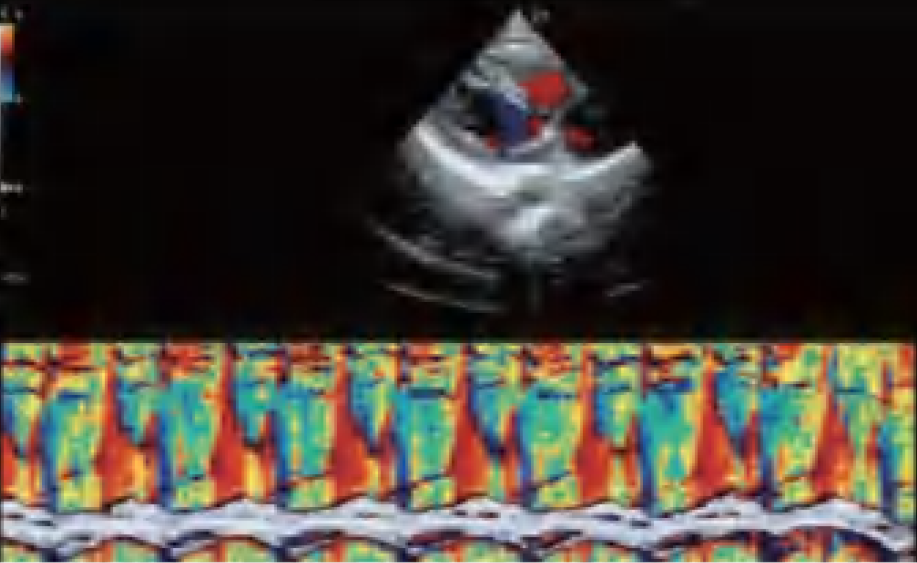

El DW-L50 Exp, impulsado por la avanzada plataforma de ultrasonido ST-U, ofrece imágenes ultra claras en todo momento. Con una movilidad y adaptabilidad sobresalientes, funciona de manera fiable en diversos entornos clínicos complejos. Su introducción permite que más instituciones médicas accedan a tecnología de ultrasonido rentable y de alto rendimiento.